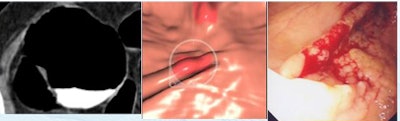

![]() |

| Two low-grade dysplastic polyps < 1 mm in height, including a "carpet" lesion, were not detected by CAD or initially at CTC (left, middle), but were later found at CTC and conventional colonoscopy (right). All images courtesy of Dr. Franco Iafrate. |

Two lesions < 1 mm in height were not detected by either CAD or the radiologists, but were found at conventional colonoscopy. Both could be seen retrospectively at CTC as a focal wall thickening.